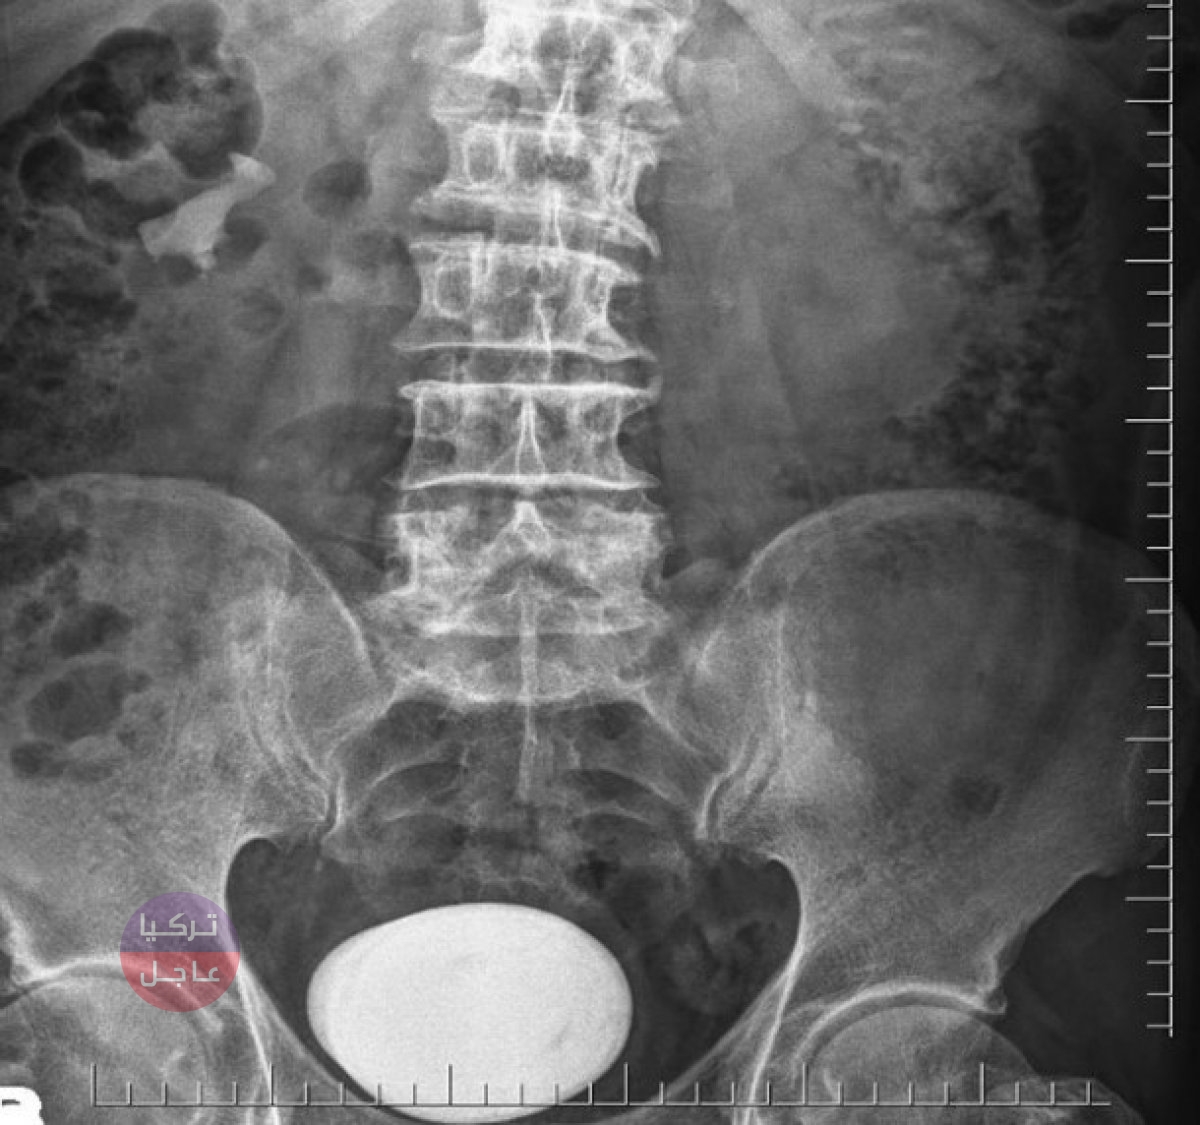

قالت وسائل اعلام تركية ، أنه في منطقة فاتسا في أوردو ، أزال الأطباء حصوة بحجم درنة البطاطس الكبيرة من مثانة مواطن تركي مريض بعدوى المسالك البولية.

نتيجة الفحوصات والتحاليل ، تم الكشف عن حصوة كبيرة جدًا في مثانة المريض. ومن النادر جدًا رؤية حصوات بهذا الحجم في المثانة ، وقوبل الحجر الخارج من مثانة المريض بدهشة كبيرة جدا.

نظرًا لأنه لم يكن من الممكن إزالة الحجر في المثانة للمريض الذي تم نقله إلى الجراحة على الفور ، فقد تم إجراء جراحة فتح حصاة المثانة.

وبدهشة الجميع ، تم بنجاح اخراج الحصوة على شكل درنة بطاطس كبيرة.